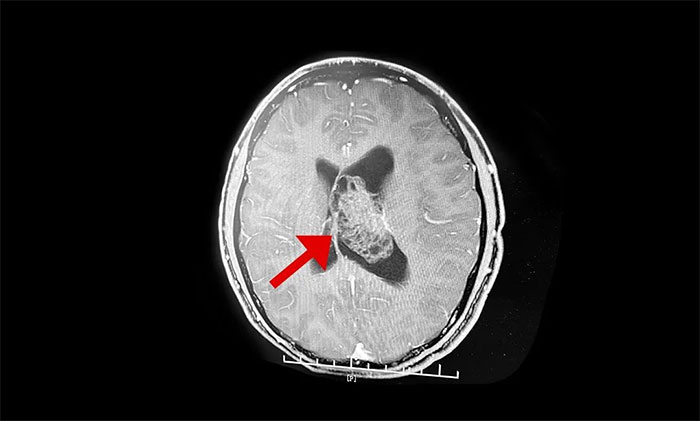

最終被診斷為中樞神經(jīng)細胞瘤。中樞神經(jīng)細胞瘤屬于比較罕見的腦腫瘤,一般直徑超過三公分即為巨大腫瘤,而李威腦室內(nèi)的腫瘤直徑竟達七公分,接近一個拳頭大小。幸運的是,順利手術(shù)切除。

上海藍十字腦科醫(yī)院神經(jīng)外科李士其教授介紹,中樞神經(jīng)細胞瘤(Central neurocytoma,CN)是少見的神經(jīng)系統(tǒng)腫瘤,1982年由Hansson首次報道并命名,2016年WHO神經(jīng)系統(tǒng)腫瘤組織學分類將其歸類為神經(jīng)元和混合型神經(jīng)元膠質(zhì)瘤(WHOⅡ級)。中樞神經(jīng)細胞瘤僅占顱內(nèi)腫瘤的0.25%~0.50%,好發(fā)于20~40歲青年人,無性別差異。病史一般較長,可達數(shù)十年之久,好發(fā)于側(cè)腦室透明隔,當病變累及Monro孔時,阻塞腦脊液循環(huán),引起頭痛、頭暈、惡性、嘔吐以及不同程度視力改變等非特異性顱內(nèi)高壓癥狀。

李士其教授介紹,該腫瘤一般生長于側(cè)腦室或三腦室,由于生長的位置處于腦室內(nèi),有較大空隙代償,疾病初期癥狀并不典型,當出現(xiàn)如頭痛、嘔吐等臨床癥狀時,瘤體已經(jīng)比較大。在治療上首先建議進行手術(shù)切除,解除腫瘤占位效應,通暢腦脊液通路,緩解腦積水,解除顱內(nèi)高壓。李士其教授指出,中樞神經(jīng)細胞瘤一般為偏良性腫瘤,若能手術(shù)全切腫瘤,或者大部分切除后輔助放療可以長期生存。所以,手術(shù)這一步非常關鍵。

▲ 非典型性中樞神經(jīng)細胞瘤

但由于腫瘤較大、血供豐富,且與腦室壁黏連明顯,致使腫瘤分離及切除異常困難。而且腦室內(nèi)血管及神經(jīng)組織結(jié)構(gòu)復雜、功能重要,如何在切除腫瘤的同時盡可能保護腦功能是手術(shù)的最大難點。